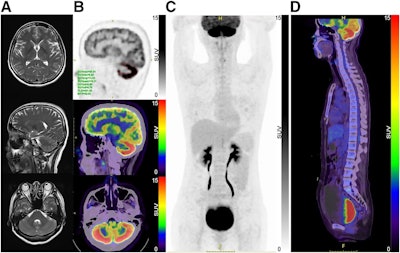

“However, F-18 FDG-PET/CT demonstrated extensive cerebellar cortex hypermetabolism. The SUVmax was 25.91,” the group wrote.

Brain MRI and F-18 FDG brain and whole-body PET/CT images. (A) No obvious abnormalities were found in axial and sagittal slices from T2-weighted MR images. (B) Whole cerebellar cortex had diffuse F-18 FDG hypermetabolism in PET/CT brain images, with SUVmax of 25.91. (C and D) Whole-body F-18 FDG-PET/CT showing distended bladder. TLG = total lesion glycolysis; MTV = metabolic tumor volume. Image and caption courtesy of the Journal of Nuclear Medicine.Brain MRI and F-18 FDG brain and whole-body PET/CT images. (A) No obvious abnormalities were found in axial and sagittal slices from T2-weighted MR images. (B) Whole cerebellar cortex had diffuse F-18 FDG hypermetabolism in PET/CT brain images, with SUVmax of 25.91. (C and D) Whole-body F-18 FDG-PET/CT showing distended bladder. TLG = total lesion glycolysis; MTV = metabolic tumor volume. Image and caption courtesy of the Journal of Nuclear Medicine.